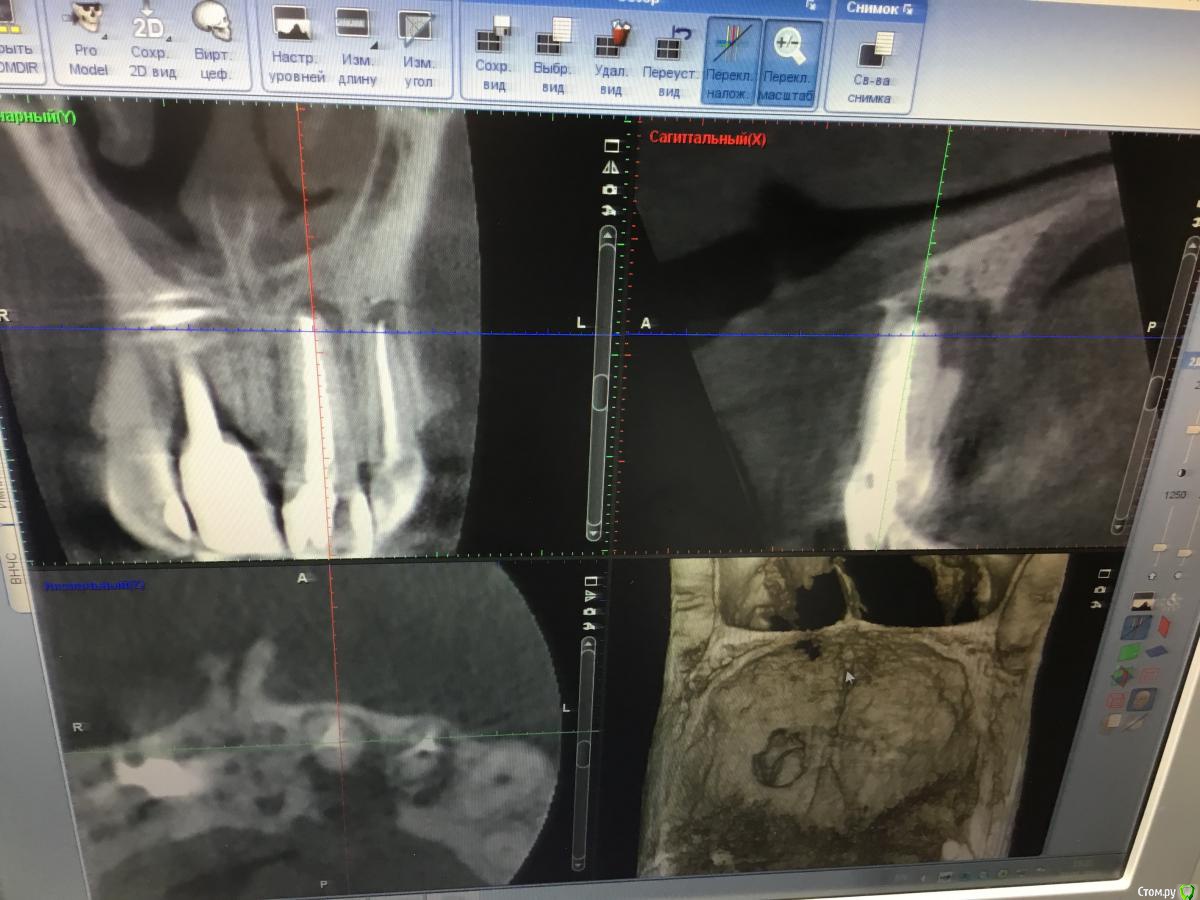

Zorrro Опубликовано 6 марта, 2016 Поделиться Опубликовано 6 марта, 2016 (изменено) Мой постоянный пациент привёл своего сынишку с жалобами на свищь на нёбе.Сделали кт и решили ,что вначале переберём каналы,а через пол года будем посмотреть куда нам двигаться дальше… Эстетика коронки на 11 вполне устраивала пациента,тем более он был уверен,что поставилимплант и вследствии коронку популярный доктор используя новейшие технологии и материалы,позволяющие не прибегать к устаревшим костным и ещё каким-то пластикам.запись к доктору уходила на пол года вперёд и молодой человек чудом втиснулся в этот плотный график,чтобы отхватить немножко и себе этих самых "новейших" технологий под нос. Фото ещё раз показывает,чтосамое главное в успехе частной практики это ВЕРА доктора в себя и то,что он делает.меня же коронка устраивала тем более,потому что переделывать её вместе с имплантом мне крайне не хотелось.обошлись комментарием про усиленную гигиену и регулярные наблюдения раз в пол года. итак занялись посильным трудом:отмыли 21 и 22,констрикция убежала за 50.02,остановились на 70.02 стальными файлами отступя 1мм,метапекс,через 2 недели irm и стекловолокно нафуджи+,филтек.договорились про контроль через пол года и коронки если всё ок. Ещё немного срезов до и преимущество кт перед прицельными снимкамиИ сразу после. Про коронки и корневой герметизм пациент не понял и решил оставить бломбы на месте. Изменено 6 марта, 2016 пользователем Zorrro 1 Ссылка на комментарий